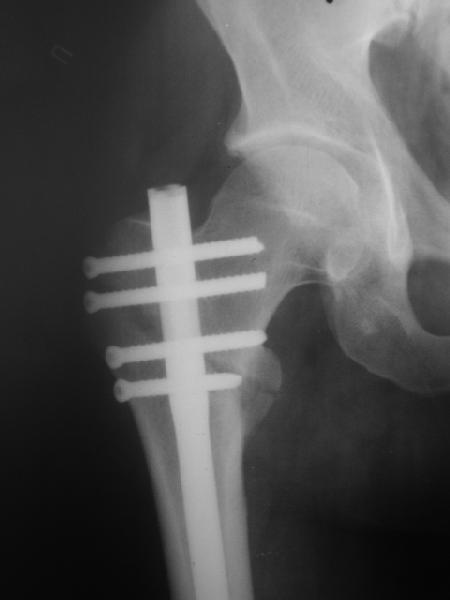

В частности, на проксимальном конце сделано еще одно дополнительное статическое отверстие. Можно ввести в проксимальном отделе 4 винта, из них 3 статические (2 в круглые отверстия и 1 по нижнему краю овального). Картинки в приложении. На дистальном конце стержня тоже кое-что улучшено. Спрашивайте в аптеках, как говорится. Выпускается предприятием "ЦИТО" (Москва), то есть это малобюджетное решение.

Конечно, мы не синтезируем остеопорозые вертельные переломы согласно прилагаемому примеру, винты 6 мм вырежутся. Но у более молодых при хорошем качестве кости такие или подобные гвозди с поперечным расположением винтов вполне применимы для меж- и подвертельных переломов.